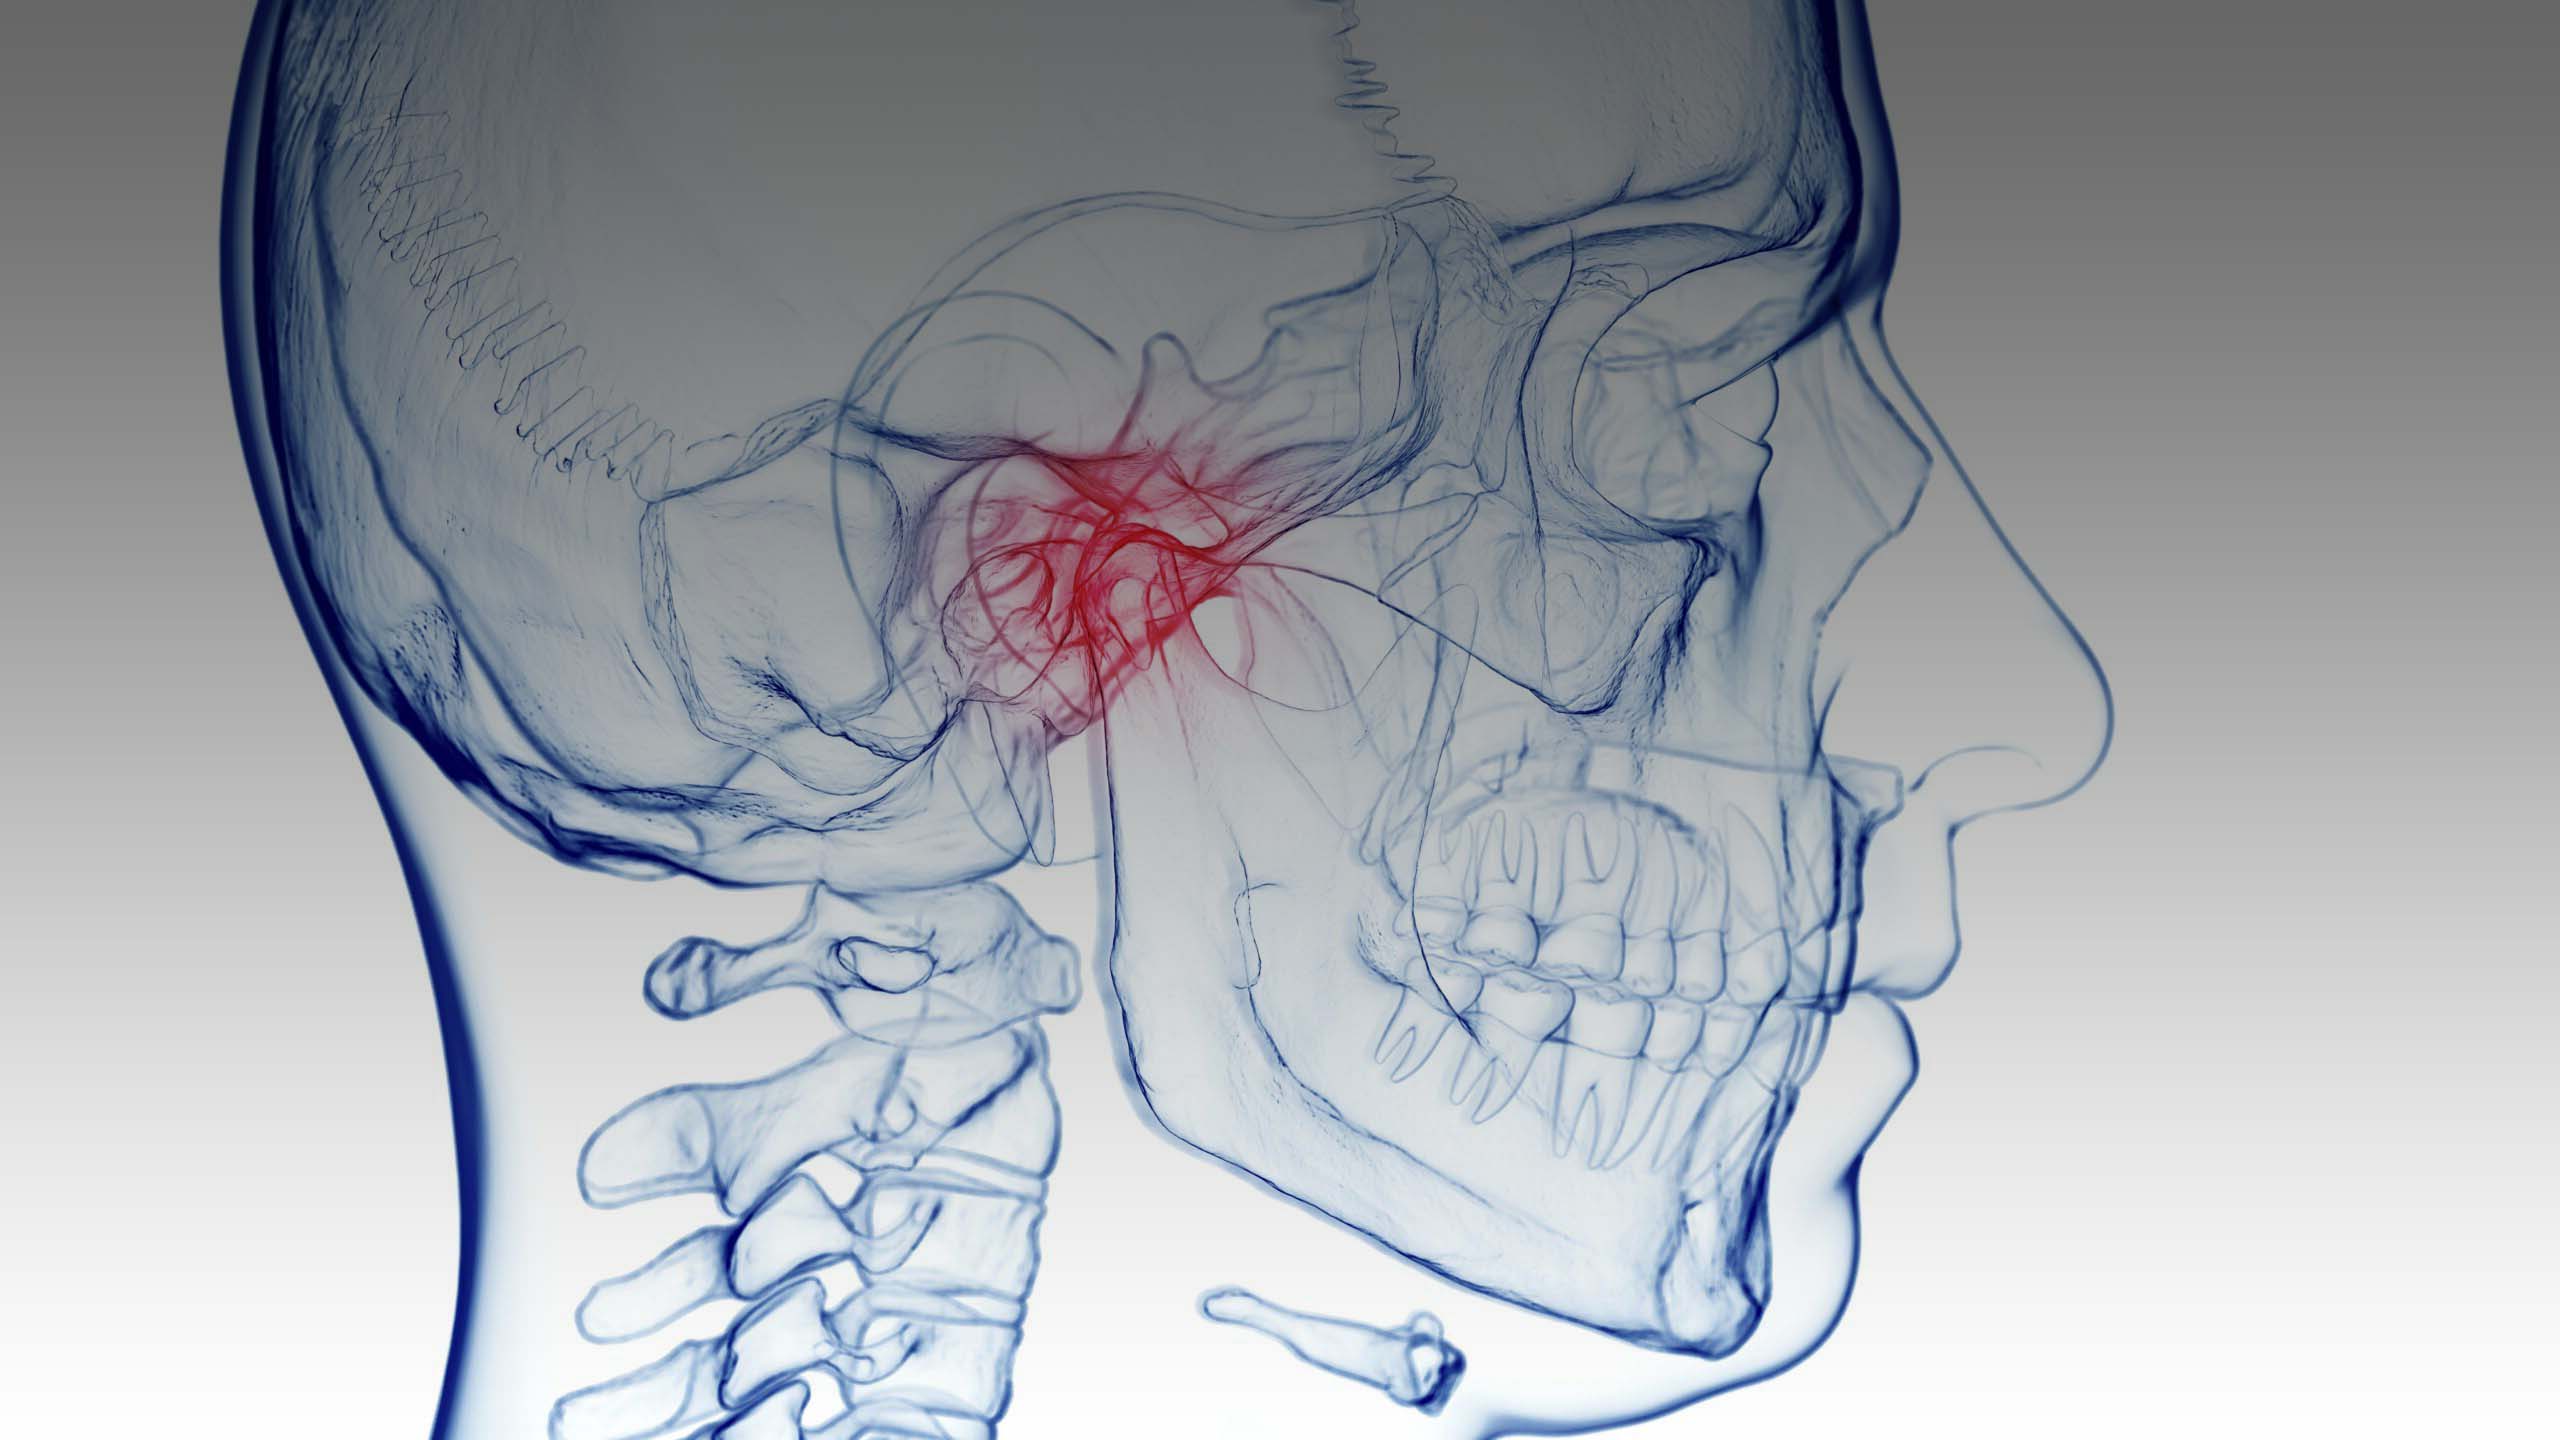

Temporomandibular disorders (TMDs) encompass a whole range of clinical problems related to masticatory musculature, temporomandibular joints (TMJs), and associated structures. These disorders are often accompanied by pain in the preauricular region, pain in the masticatory muscles, TMJs, and associated hard and soft tissues of the oral cavity. Other symptoms include limitation or deviation in the movement of the lower jaw, sounds in the TMJ, and/or headaches and facial pain.

In the temporomandibular joint, painful skipping, dislocation of the disc, or the formation of arthritic changes can occur, also accompanied by pain. Ringing in the ear (tinnitus) may occur.

Possible pain in the muscles of the head, neck, and shoulders, due to their overexertion or shortening, can also occur. Chronic headaches, muscle pain in the head and neck, dizziness, reduced mouth opening, swallowing problems, increased sensitivity to light are frequent symptoms in these patients. Since the position of the jaw affects the statics of the whole body, if it is irregular, the body is no longer in balance and one side of the body (hip, knee, and foot) is more burdened. We call this set of conditions temporomandibular disorders, which often remain unrecognized due to their wide range of symptoms.